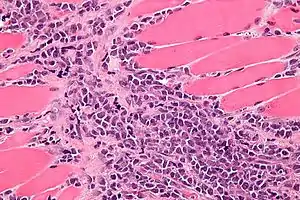

Micrograph of a myeloid sarcoma within muscle. H&E stain.